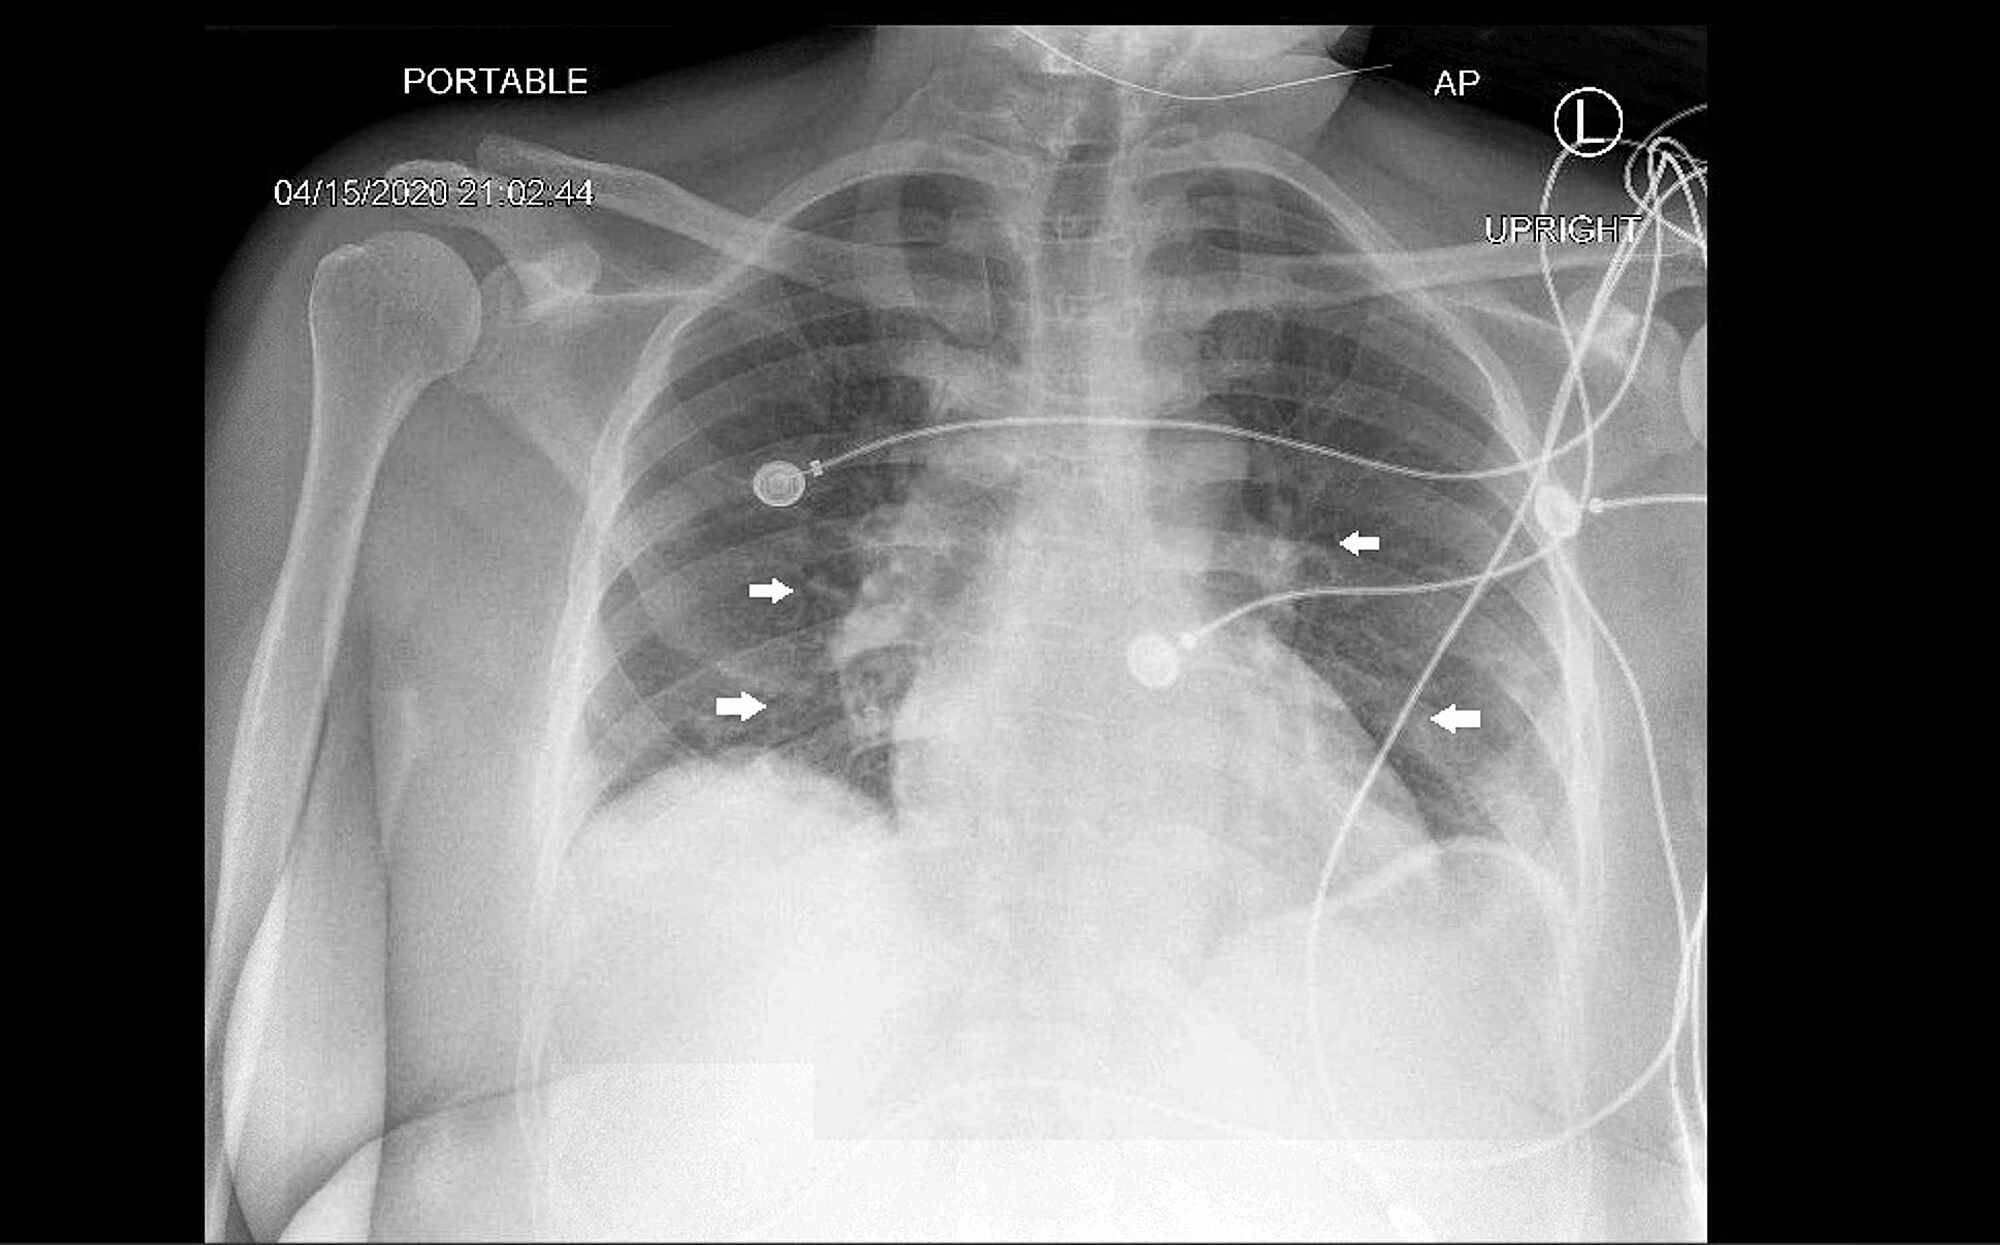

From pubs.sciepub.com

Figure 2. Portable AP Chest Xray from present hospitalization Chest X Ray Myocarditis Learn about the symptoms, diagnosis, and treatment of myocarditis. Specifically, this is an infection of the myocardium, which is the middle layer of the heart wall. Myocarditis is a disease marked by the inflammation of heart muscle. Will often be normal in myocarditis, but it may show. Myocarditis is a condition where the heart muscle becomes inflamed. Myocarditis refers to. Chest X Ray Myocarditis.